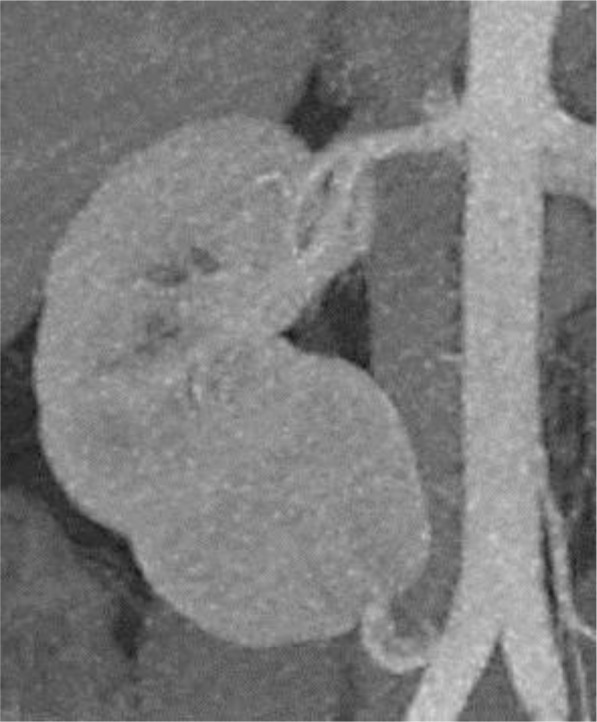

Within the evaluation process of living kidney donors, split renal function is usually evaluated by renal scintigraphy. Since split renal function measured by conventional posterior scans depends on the position of the kidney, actual suitable donors may be rejected because of an inaccurate examination technique. We report the case of a 28-year-old male living kidney donor. Due to a complex vascular anatomy of the right kidney, only his left kidney was considered eligible for transplantation. In conventional posterior Tc99m-mercapto-acetyltriglycine scintigraphy, the left kidney had a relative function of 60%. A second scintigraphy using anterior and posterior dimercaptosuccinic acid scans with calculation of the geometric mean showed an adapted relative function of the left kidney of 53%, now meeting the inclusion criteria for living kidney donation. This case shows that the geometric mean method using simultaneous anterior and posterior views obtained with a dual-head gamma camera can be a very helpful approach to determine split renal function of potential living kidney donors. Further investigation is necessary to prove the benefit of a general bilateral scan before living kidney donation.